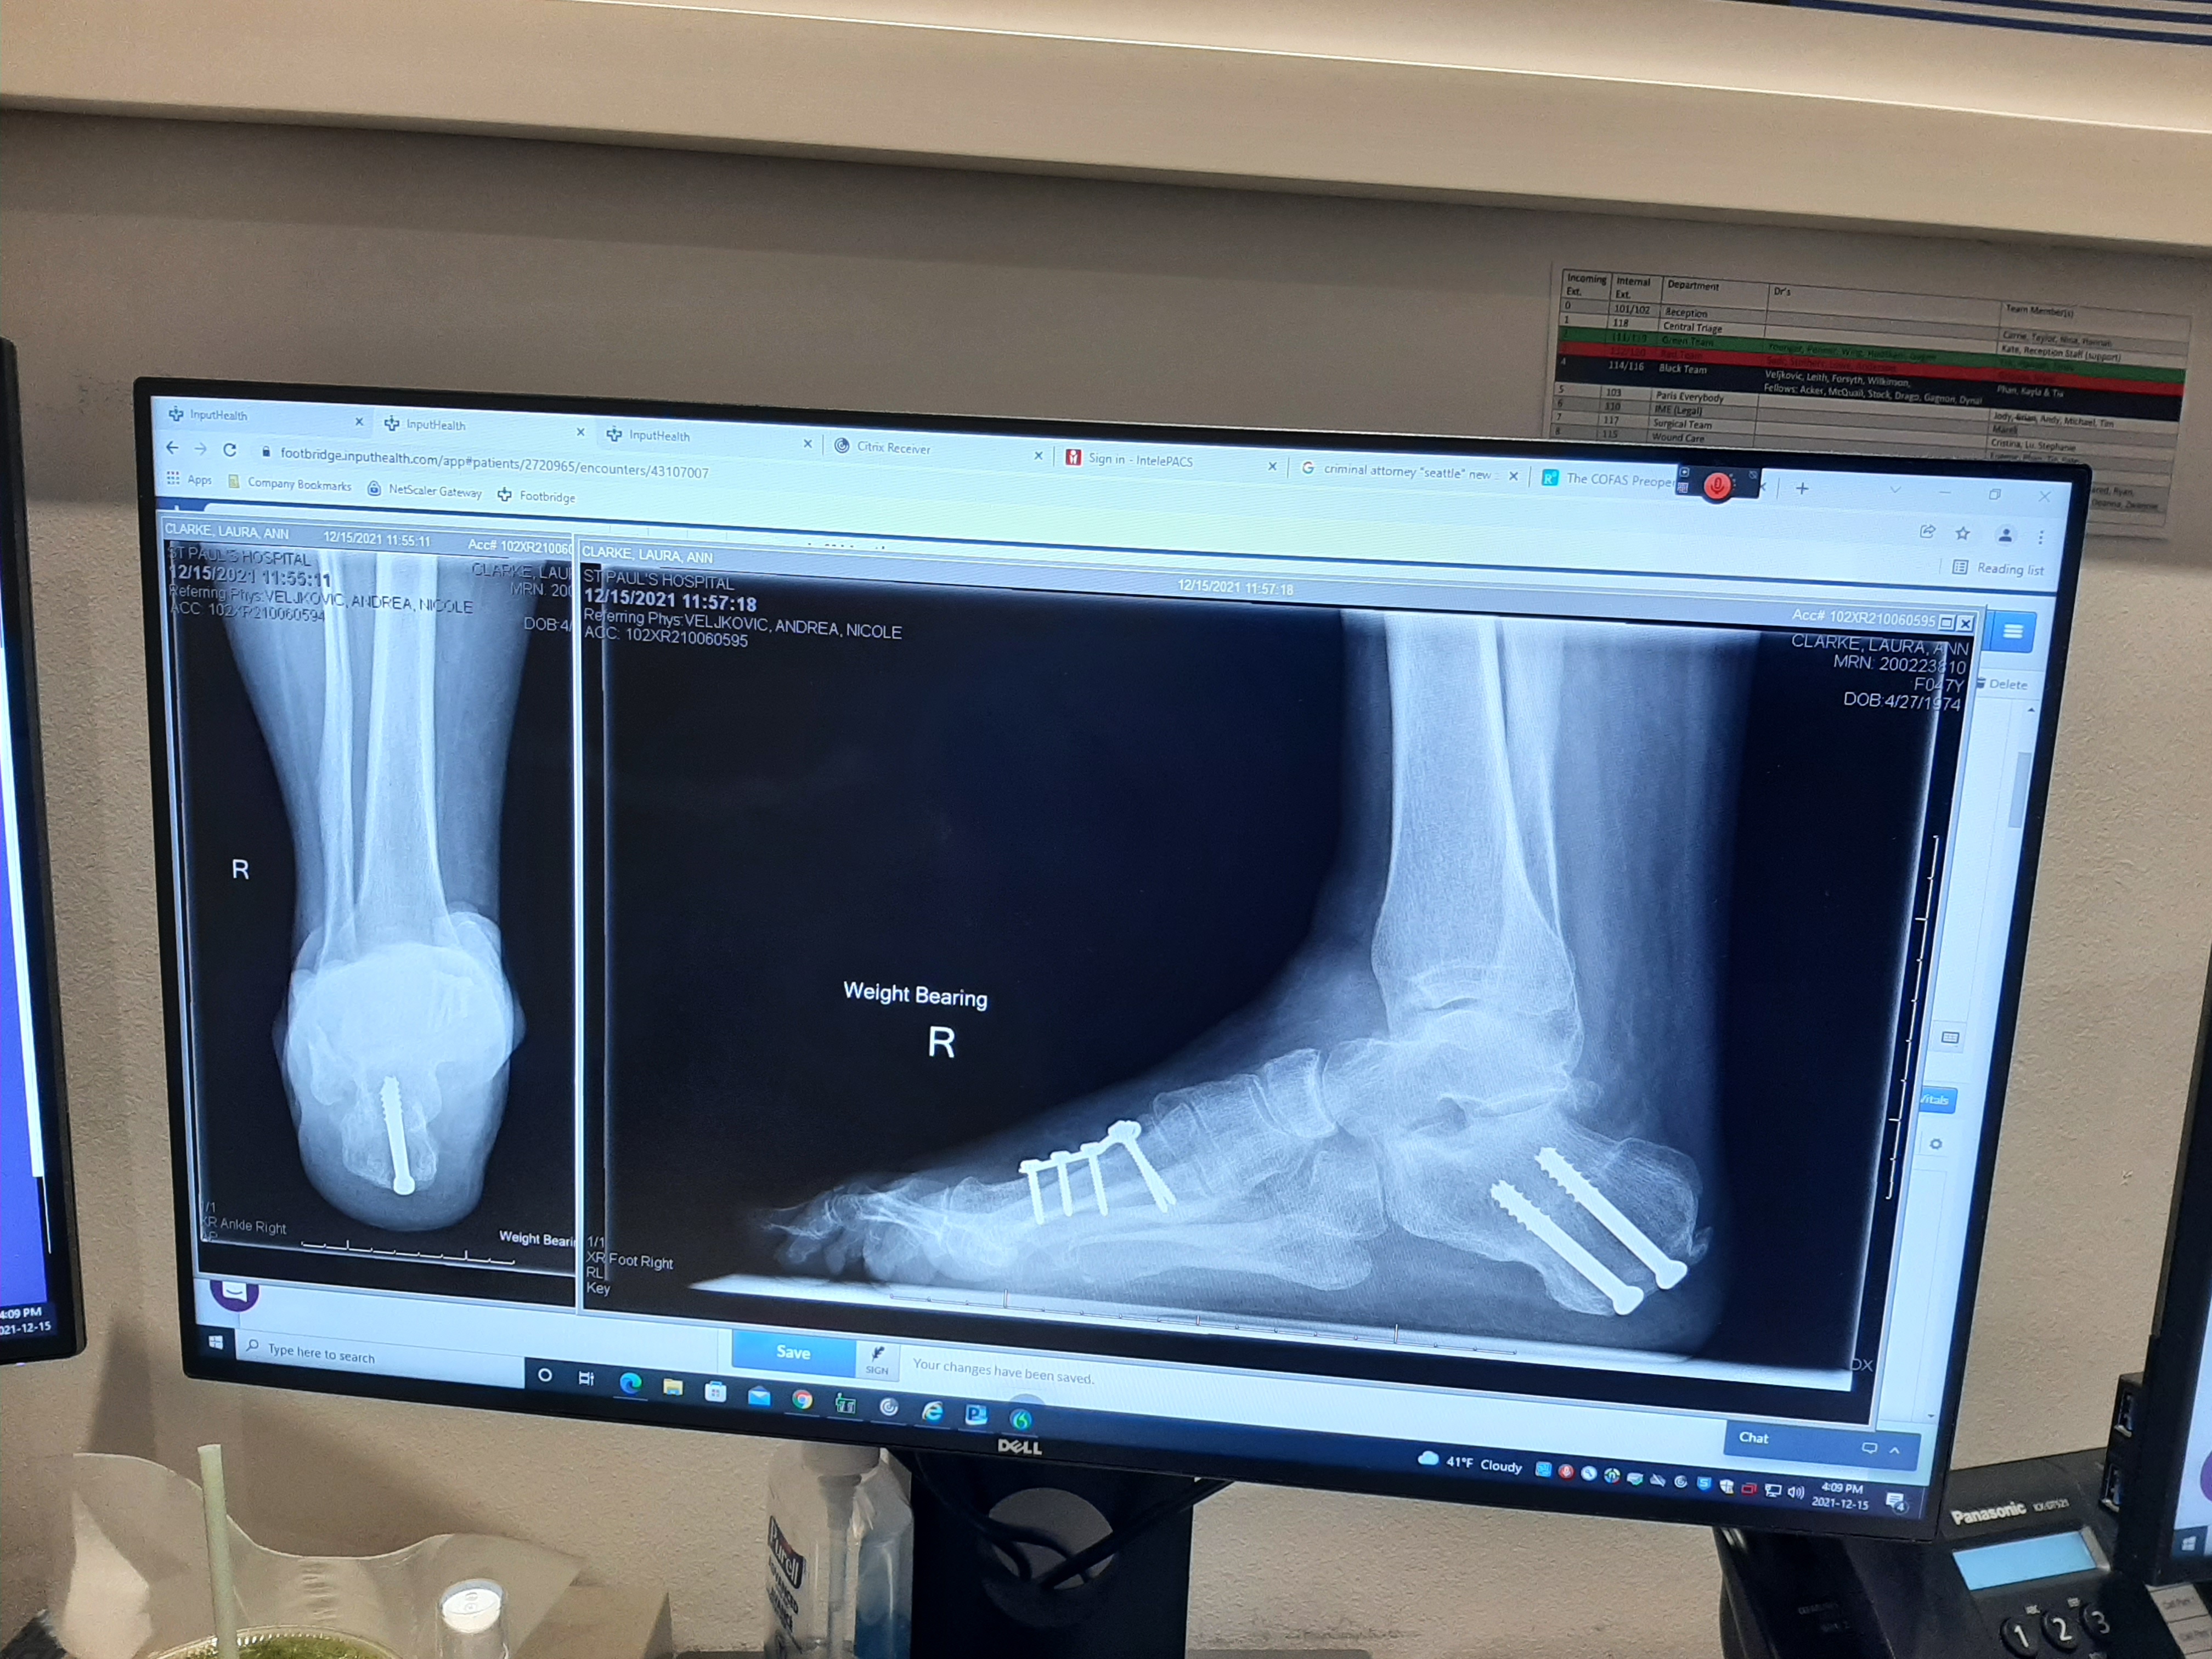

i waited an hour and a half on bed 3 until it was my turn to see dr andi.  that's normal at footbridge.  she was cheerful and optimistic and confident as always.  she said my xrays looked beautiful and was quite happy with my progress. today she was accompanied by the swiss antoine.  it was my first time meeting him.  she asked about what pain i still have and explained why it feels like there is no padding in my heel. something about when you move it...there's no fat... and an orthotic would help or even a gel pad.  and that my ankle has some scar tissue.  she also said she had quite a time creating a balance with my toes.  she said she went up and down and up and down.  i'm not sure what that means exactly except i'm grateful that she puts so much effort and excellence into her work.  i asked her about my sleeping splint and she said i only have to wear it once or twice a night.  haha.  but she meant week.  and she said she would see me in 6 months but if i needed to come in i could.  there's an open door policy.

i asked to see my xrays